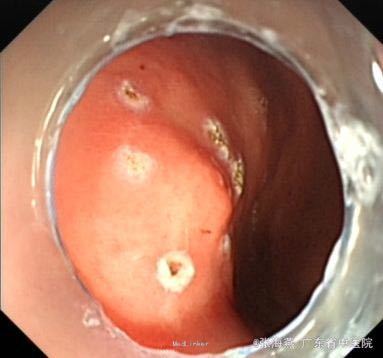

体格检查:BP:146/87mmHg;腹平坦,未见胃肠型及蠕动波,腹软,未扪及包块,上腹部轻压痛,无反跳痛,肝脾肋下未扪及,肝肾区无叩击痛,麦氏征(-),莫非氏征(-),移动性浊音(-),肠鸣音5次/分。 辅助检查:血型:B型,RhD阳性;血常规、二便常规、凝血、生化、肝功、CEA、CA199、输血4项未见异常。心电图:窦性心律,心脏逆钟向转位。胸片:主动脉硬化;胸椎退行性变。B超:胆囊壁稍毛糙,肝脏、胰腺、双肾、膀胱未见明显异常。超声胃镜:胃底固有肌层隆起:符合胃底间质瘤改变;慢性浅表性胃窦炎。

诊断:1.胃底间质瘤(ESD术后);2、慢性胃炎;3、高血压病2级;4、颈椎退行性变。 治疗:治疗上,行ESD术切除胃底肿物,术后予明可欣静滴预防感染,潘妥洛克静滴抑酸护胃,铝镁加混悬液口服保护胃粘膜,以及补液营养支持治疗。术后病理提示:符合胃肠道间质瘤(低级别,无风险);经治疗后,患者无特殊不适,予出院。